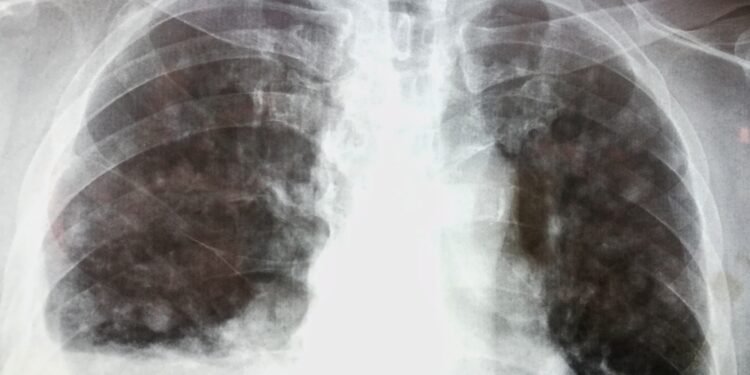

- Vertinama ir širdies veikla – gali būti atliekamas širdies biopsijos, magnetinio rezonanso ar elektrokardiogramos tyrimai.